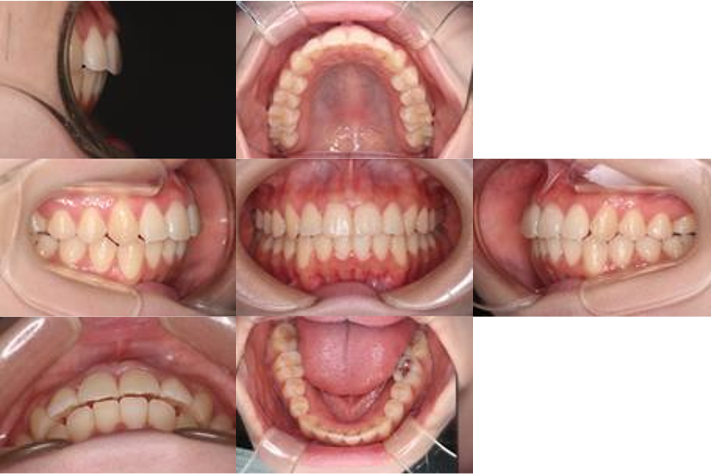

治療計画

前歯が噛み合っていない(開咬)だけでなく、出っ歯気味(オーバージェット)で、犬歯に噛み合わせのズレ(II級)があり、さらにねじれた歯(捻転)があります。これらを解消し、お口元が綺麗に閉じる状態を目指しました。

IPR(歯と歯の間を削る処置)と顎間ゴムを行いながら、インビザラインで開咬を治療する計画を立てました。

治療をしながら、MFT(口腔筋機能療法)も行っていくことにしました。